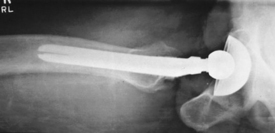

(Axiolateral Inferosuperior Projection [Danelius-Miller Method])

• Supine, no rotation of pelvis

• Flex unaffected knee and hip and provide support such as the x-ray tube (use pad or towels for possible hot collimator).

• Rotate affected leg internally 15° unless possible hip fracture.

• Place vertical grid IR against side just superior to iliac crest with plane of IR perpendicular to CR.